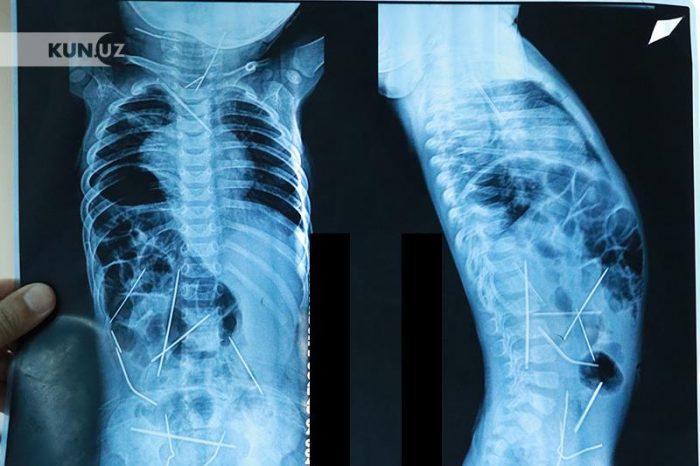

ადგილობრივი გამოცემის „kun.uz“ -ის ინფორმაციით, ექიმებმა ბავშვის სხეულში ნემსები მას შემდეგ იპოვეს, რაც მისმა დედამ დახმარებისთვის მიმართა და ჩვილს რენტგენი გადაუღეს. მას რესპუბლიკურ სამედიცინო ცენტრში სასწრაფო ოპერაცია ჩაუტარდა. ბავშვთა განყოფილების უფროსმა, პროფესორმა აკიმოვმა განაცხადა, რომ რადგან ნემსები სხეულის სხვადასხვა ნაწილში იყო, მათ ბავშვი დამოუკიდებლად ვერ გადაყლაპავდა – „ცხრა საათიანი ოპერაცია ჩატარდა, ჩვილის სხეულიდან 13 ნემსი ამოვიღეთ, ხოლო დანარჩენ 3 ნემსს, პაციენტის ასაკის გათვალისწინებით, მომდევნო ოპერაციაზე ამოვკვეთთ“. პროფესორის თქმით, ახლა პაციენტი რეანიმაციულ განყოფილებაში იმყოფება.